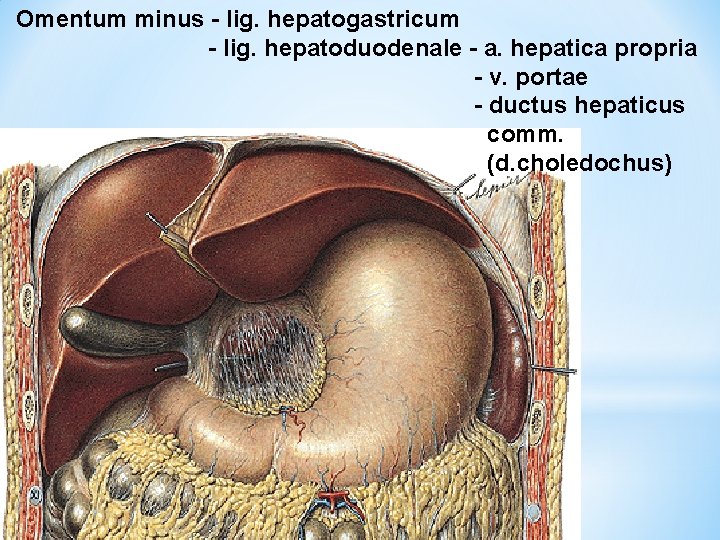

Omentum minus - lig. hepatogastricum - lig. hepatoduodenale - a. hepatica propria - v. portae - ductus hepaticus comm. (d. choledochus)